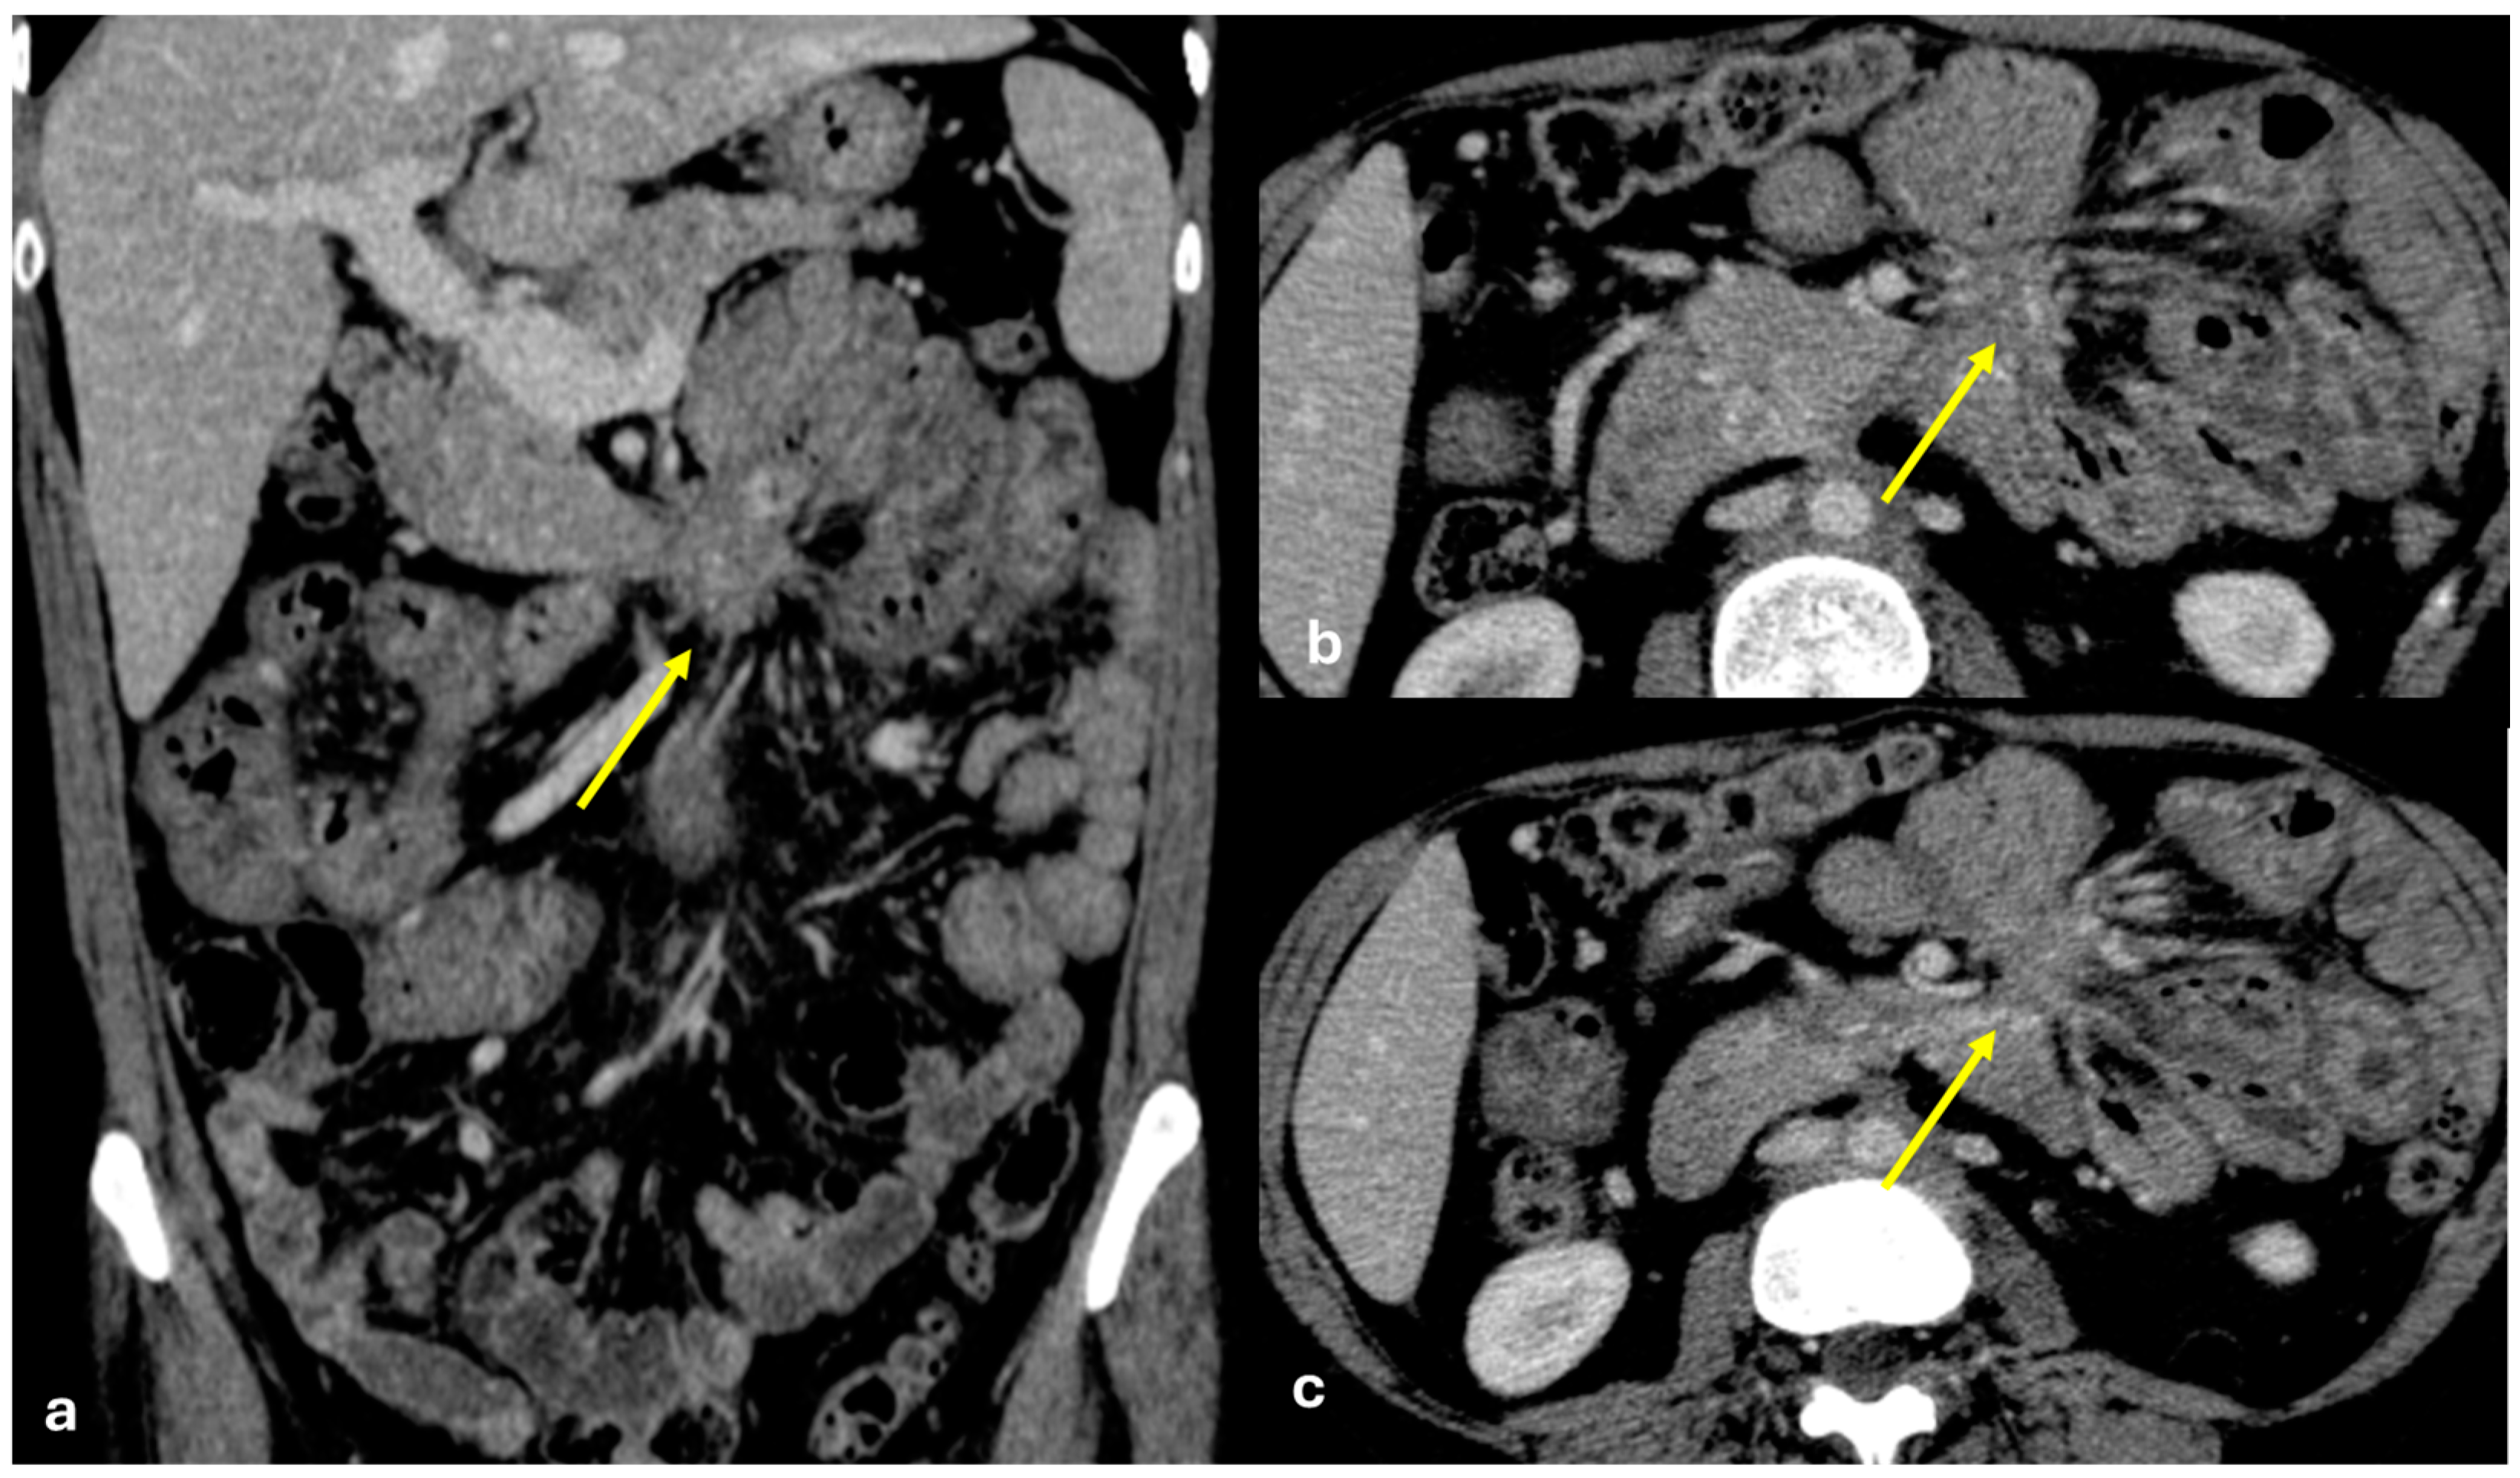

3.1.6. Mesenteric Metastases from Ileal Neuroendocrine (Carcinoid) Tumors